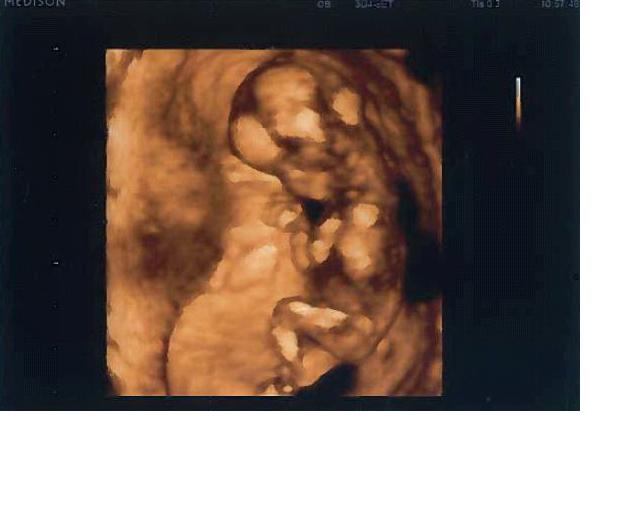

Jinak holky vše v pořádku, mužíček byl na měkko

pořád sebou mrskal, už máme 12 cm a dostala jsem i fotečku, tu přikládám, jen to oskenování tam hodilo pár odlesků, ale tak to neva...Naživo to bylo něco nádherného...Chlapíček hned že tam vidí pindíka, a tak mu doktor musel říct že je to šňůra, ale pak říká, tak ve vašem případě je to naprosto jasné...ale co? Tak že by ten chlapeček?

Chlapíček byl na měkko, bylo to nádherný, posílám fotku, jen pár odlesků od toho skenování tam být nemělo, ale tak celkově asi víte, co si máte představit

Máme už 12 cm a chlapíček a kdy uvidíme pinďourka a on že příště,ale pak se tam prdelka točil a on říká, tak ve vašem případě to je naprosto jasné ne? Tak nevím, jesi tam něco viděl, já viděla teda asi šńůru

Jé, ten tam ale krásně hajá! Wiwuš, nádhera!

[187803] No ani moc nehajal, pořád se právě natáčel a obracel, ale ksiftík hned odvrátil, takže do tváře se nesmíme asi ještě dívat, ale klín právě natáčel, ale ta šňůra tam lítala, nebo co to bylo, já nevím..To jsem jen vyjančená, že si toho kloučka přejeme